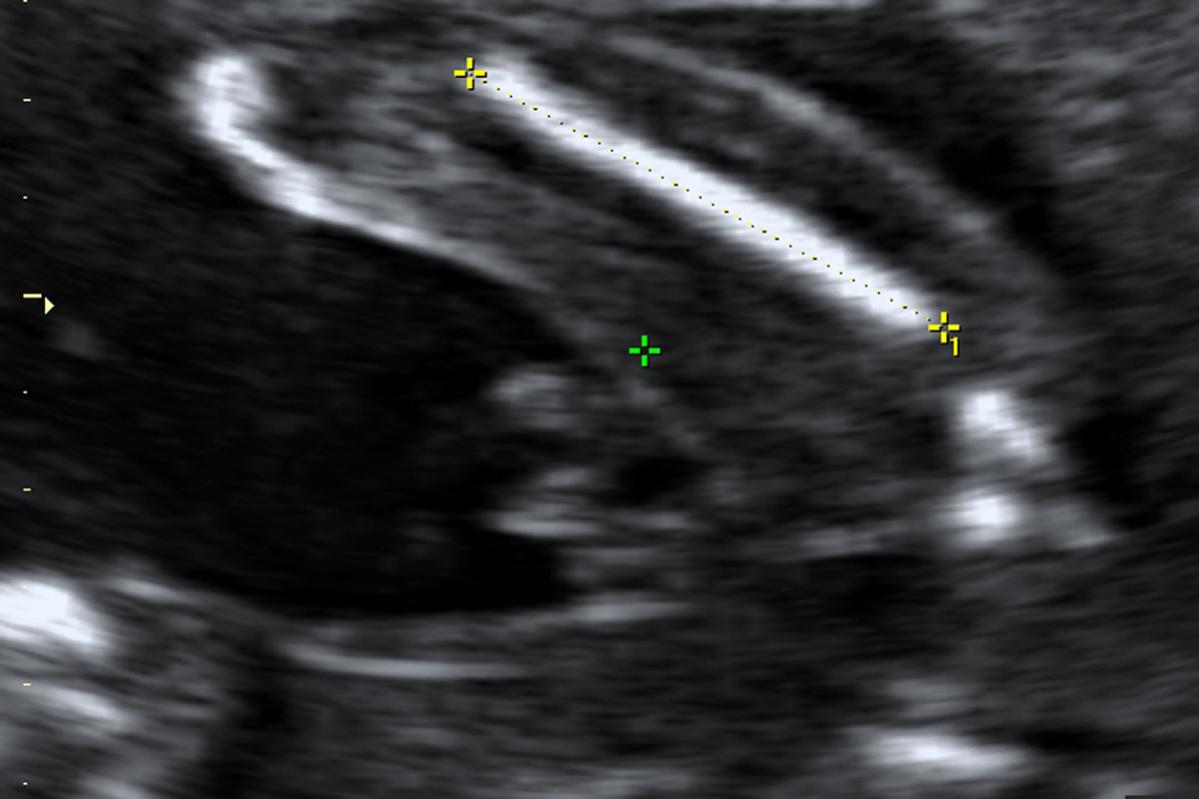

The marking on the image is of the thigh bone.Attachment 804

It's a little...different...than normal boy ultrasounds. I'd lean boy due to the absence of girl parts + the presence of what looks to be boy parts.

I say boy... my boys parts looked like that. My u/s tech called it the turtles back.